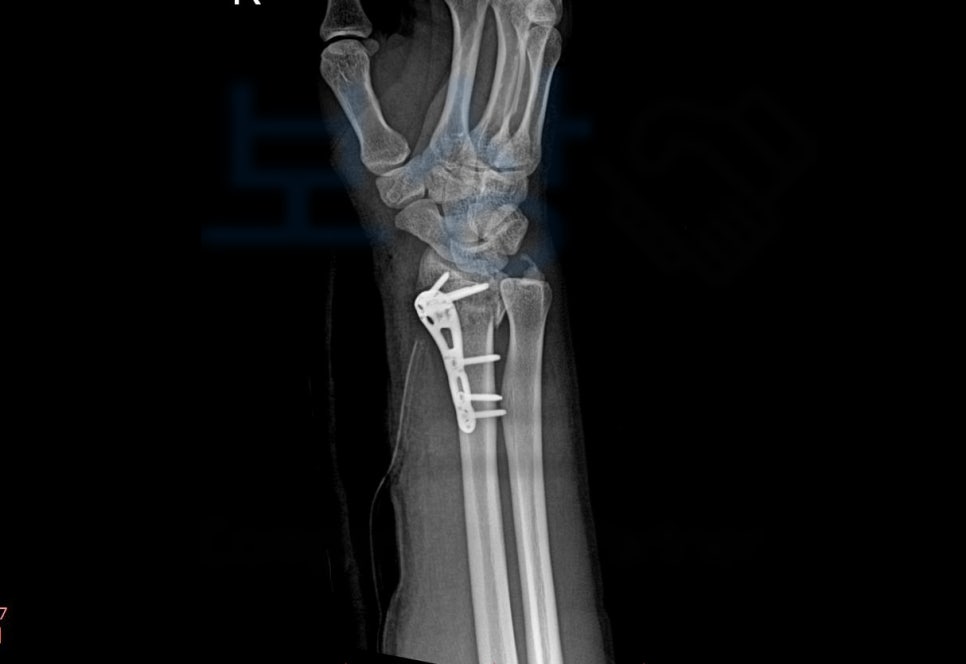

이 사고로 손@@님은 응급실에 내원하셨고

요골 하단의 골절, 즉 손목 골절을 진단받아 금속 고정 후 석고기브스 치료를 받게 되었습니다. 먼저 합의금은 구성 요소는